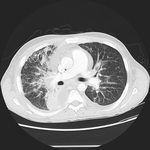

CT scan of the chest showing a reticular pattern due to pulmonary involvement by Kaposi's sarcoma

From the collection of Dr Bruce J. Dezube; used with permission